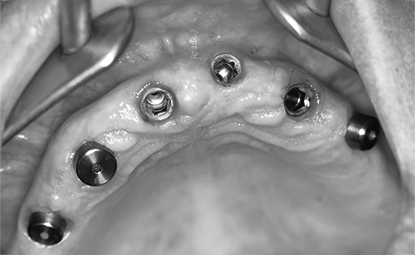

임플란트 식립

임플란트가 들어갈 위치에 무치악 임플란트를 이식,

잇몸을 엎어 잇몸뼈간의 결합을 유도합니다.